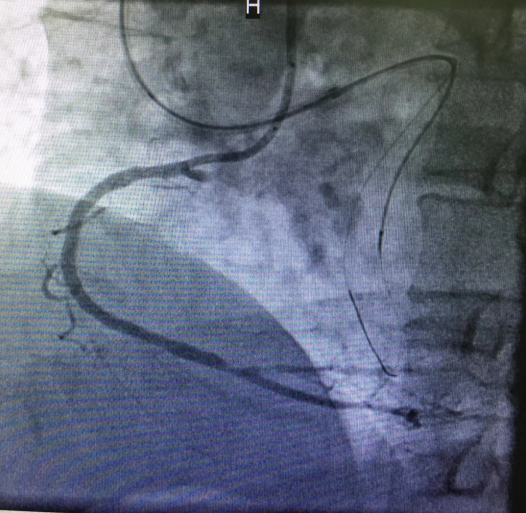

心内三完成男同视频 首例逆向开通冠脉CTO病变